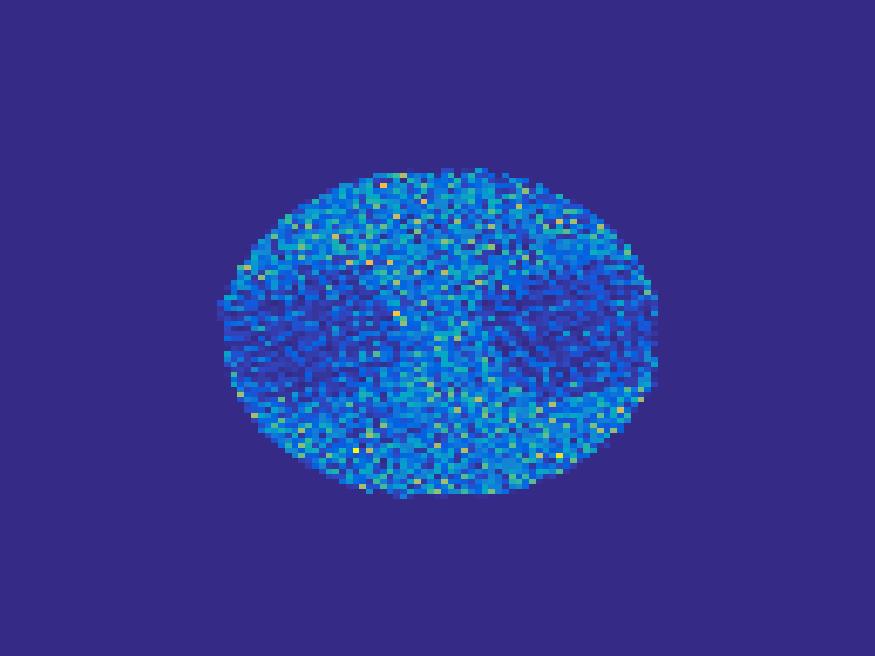

The proposed method is tested on numerical phantoms for a proof of concept study. We simulate image frames of size and projections per frame. Three time activity curves (TAC) for blood, liver and myocardium, previously used in [14] (see Figure 1), are used to simulate the dynamic images. The first simulated dynamic phantom is composed of two ellipses. In temporal direction, the positions of the two ellipses are stationary while the intensity in 90 frames within the region of each ellipse is generated according to the TAC of blood or liver. The projections are generated by using Radon transform sequentially performed for each frame.

In the tests, projections at two orthogonal angles are simulated for every frame to mimic 2-head camera data collection. The projection angles increase sequentially by along temporal direction. For example, at frame 1, projections are simulated at angle and , and at frame 2, angle and , etc. Finally, white Gaussian noise is added to the projection data. Reconstruction results with different methods are shown in Figure 3. Since the number of projections is very limited for each frame, the traditional FBP and least square methods cannot reconstruct the images satisfactorily, while the proposed method is capable to reconstruct the images effectively. Compared with SEMF model, when the edge of images jump (see frame 21 -frame 31 in Figure 3), the proposed model can better capture the change of the tendency of TAC.

| Frame 1 | Frame 11 | Frame 21 | Frame 31 | Frame 41 | Frame 51 | Frame 61 | Frame 71 | Frame 81 |